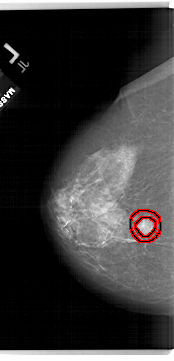

A_1622_1.RIGHT_CC

RIGHT_CC LINES 6481 PIXELS_PER_LINE 3331 BITS_PER_PIXEL 12 RESOLUTION 43.5 OVERLAY

FILE: A_1622_1.RIGHT_CC.OVERLAY

TOTAL_ABNORMALITIES 1

ABNORMALITY 1

LESION_TYPE MASS SHAPE IRREGULAR MARGINS ILL_DEFINED

ASSESSMENT 4

SUBTLETY 2

PATHOLOGY MALIGNANT

TOTAL_OUTLINES 1

BOUNDARY